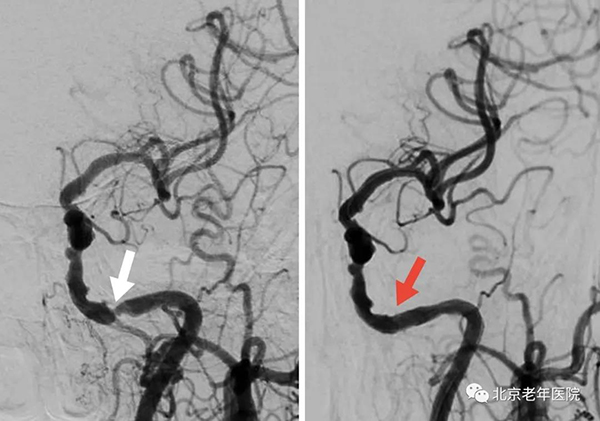

术中造影显示:左侧颈内动脉岩骨段重度狭窄(白箭头)。全麻下同期行左侧颈内动脉颅内段支架置入术(红箭头)。术后患者恢复良好,未再出现右手麻木、无力的症状。